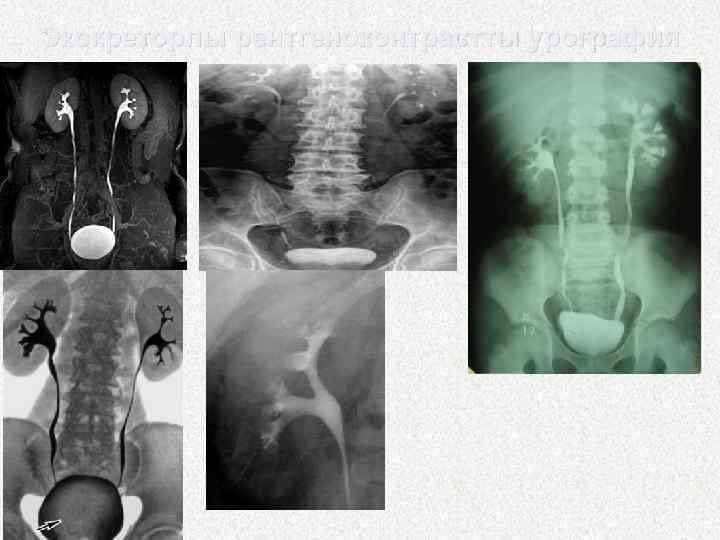

• Рентгенурологиялық зерттеу әдістері • Бұлар конкременттің химиялық құрамына қарай (рентген-оң және рентген-теріс) тастың 10 процентіне дейін рентген-теріс болады. • Жалпы урография - нефрограмманы, бел бұлшық еттерінің көлеңкесін, сүйек жүйесінің күйін жөне несеп шығатын жолдар бойындағы тасқа күдіктенетін келеңкелерді, оның орнын, өлшемі мен мелшерін бағалауға мүмкіндік береді. • Экскреторлық урография (контраст заттар - уротраст, урографин, верографин, триомбраст, омниопак, ультравист жөне т. б. ) бүйректін секреторлык-эвакуаторлық (дер кезіндегі немесе баяулатылған) қызметін бағалауға, бүйрек пен несеп жолының барлық бөлімдерінің анатомиялық-функционалдық күйін, конкременттің бар-жоғын және обструкциялық дәрежесін анықтауға мүмкіндік береді

Экскреторлы рентгеноконтрастты урография